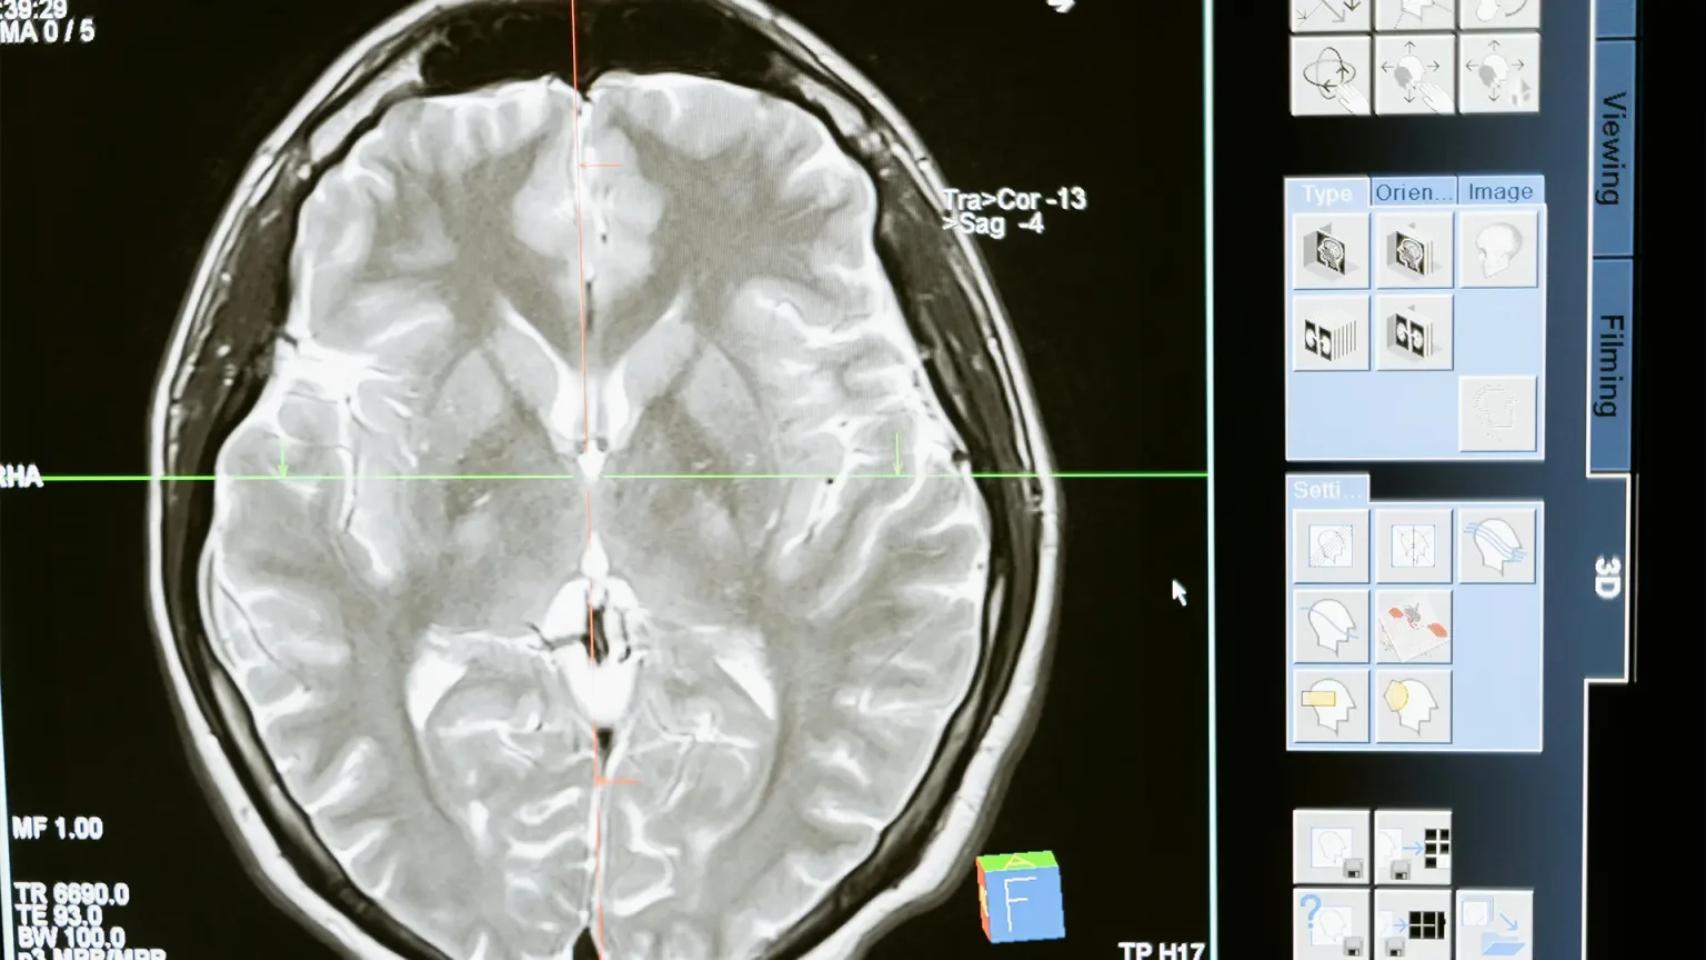

Este porcentaje supone que el deterioro que normalmente se esperaría en un año se retrasaría hasta cuatro con el tratamiento, que se administra en una cirugía cerebral que dura entre 12 y 18 horas.

En el caso de que suceda, sospecha que el principal reto será cómo conseguir que se pueda extender su uso, puesto que se administra directamente en el cerebro mediante una intervención neuroquirúrgica.

Para ello, han recurrido a "centros de excelencia en EEUU, Cardiff y Varsovia". Pero habría que encontrar una mejor forma de hacer esta cirugía para que sea "rápida, eficiente y de una manera rutinaria".